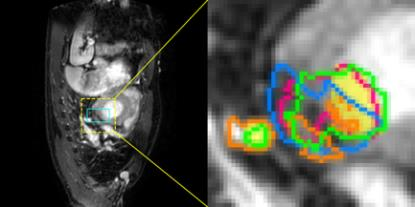

Accurate magnetic resonance imaging (MRI) segmentation is crucial for clinical decision-making, but remains labor-intensive when performed manually. Convolutional neural network (CNN)-based methods can be accurate and efficient, but often generalize poorly to MRI's variable contrast, intensity inhomogeneity, and protocols. Although the transformer-based Segment Anything Model (SAM) has demonstrated remarkable generalizability in natural images, existing adaptations often treat MRI as another imaging modality, overlooking these modality-specific challenges. We present SAMRI, an MRI-specialized SAM trained and validated on 1.1 million labeled MR slices spanning whole-body organs and pathologies. We demonstrate that SAM can be effectively adapted to MRI by simply fine-tuning its mask decoder using a two-stage strategy, reducing training time by 94% and trainable parameters by 96% versus full-model retraining. Across diverse MRI segmentation tasks, SAMRI achieves a mean Dice of 0.87, delivering state-of-the-art accuracy across anatomical regions and robust generalization on unseen structures, particularly small and clinically important structures.